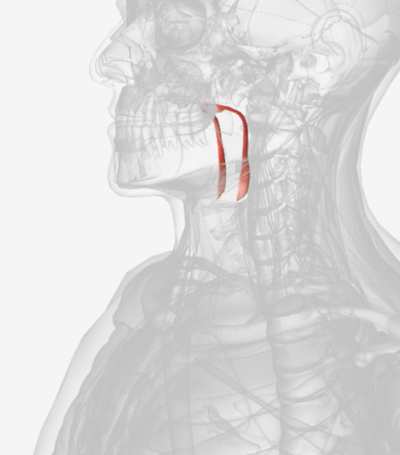

Cricopharyngeus

origin is the cricoid cartilage, coursing back to the orifice of the esophagus; function is to constrict the superior orifice of the esophagus; also referred to as the upper esophageal sphincter

Also know as the cricopharyngeus

cricopharyngeus

Also known as Upper Esophageal Sphincter